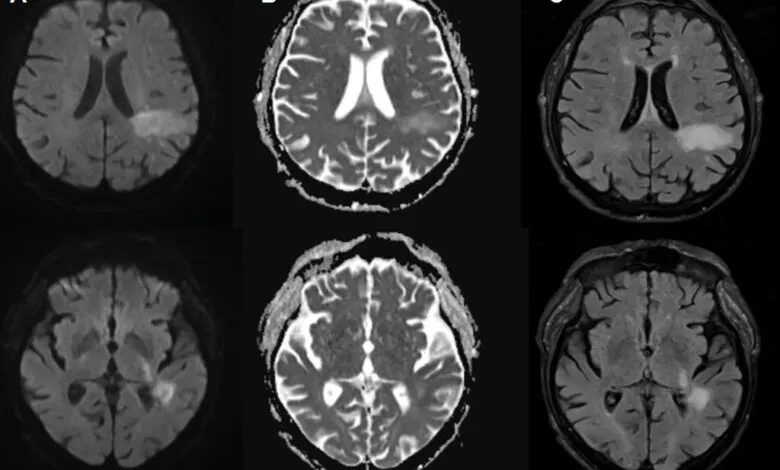

Diagnosing PML involves identifying characteristic lesions on brain scans and detecting the virus’s genetic material in spinal fluid. The symptoms, however, are notoriously variable and can be mistaken for other neurological disorders like stroke or multiple sclerosis. Patients may experience a rapid decline, suffering from speech difficulties, vision loss, impaired movement, and seizures.